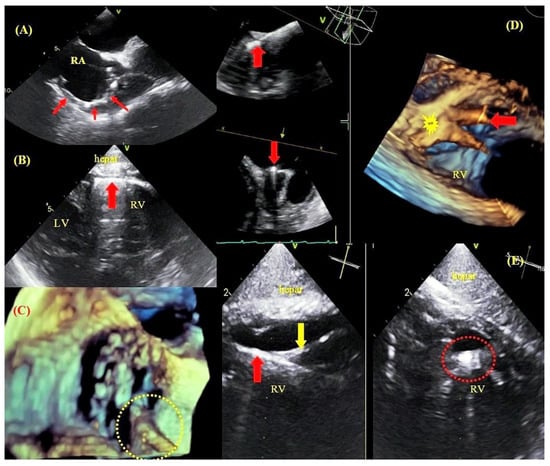

2.3. Transesophageal Echocardiographic Monitoring